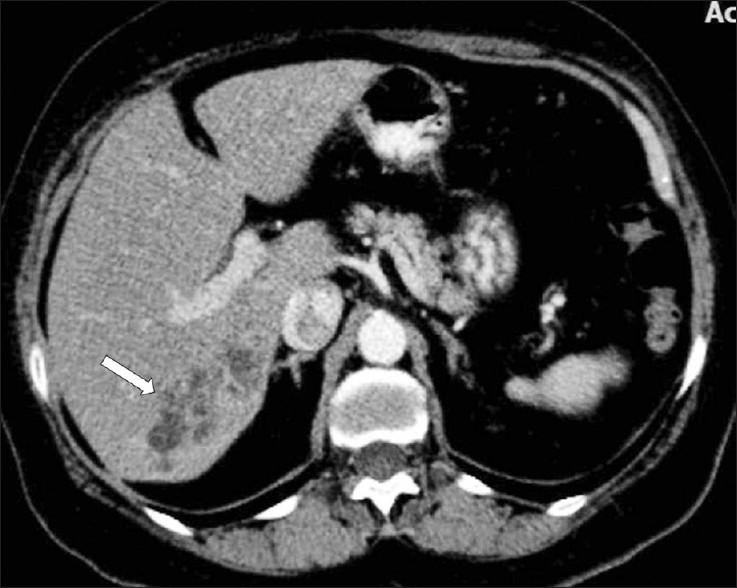

Fascioliasis refers to a zoonosis caused by Fasciola hepatica, a trematode infecting herbivores, but also occurs in humans who ingest the metacercaria found in fresh water plants. Infection in humans is common in developing countries and is also not uncommon in Europe. Diagnosis of this infection is difficult, as the history and symptoms are nonspecific and stool analysis for eggs is negative until the disease is in an advanced state by when the parasite has reached the biliary system. The clinical course consists of two phases; first a hepatic parenchymal phase in which immature larvae invade the liver parenchyma, followed by a ductal phase characterized by the excretion of larvae into the bile ducts. Parenchymal Phase: Ultrasonography (US) findings are nonspecific in this early phase. Computerized tomography (CT) may demonstrate subcapsular low attenuation regions in the liver. Magnetic Resonance imaging (MRI) can also be utilized to establish liver parenchymal involvement, and is better than CT in characterizing hemorrhagic lesions, as well as identifying more lesions relative to CT. Ductal Phase: US examination is most useful at this stage, with its ability to demonstrate the live movement of the worms within the dilated ducts. A CT demonstrates dilated central biliary ducts with periportal tracking, whereas, mild ductal dilatation is poorly appreciated under MRI. Therefore, familiarity with the multimodality imaging features of fascioliasis, in combination with an available confirmatory enzyme-linked immunoassay, would be most helpful for early diagnosis.

肝片吸虫病是一种由肝片吸虫引起的人畜共患病,这种吸虫感染食草动物,但人类摄入淡水植物中的囊蚴后也会感染。在发展中国家,人类感染这种疾病很常见,在欧洲也并不罕见。这种感染的诊断很困难,因为病史和症状不具有特异性,而且在疾病发展到晚期寄生虫进入胆道系统之前,粪便虫卵分析一直呈阴性。临床病程包括两个阶段:首先是肝实质期,未成熟幼虫侵入肝实质,随后是导管期,其特征是幼虫排入胆管。实质期:在此早期阶段,超声检查(US)结果不具有特异性。计算机断层扫描(CT)可能显示肝脏包膜下低密度区域。磁共振成像(MRI)也可用于确定肝实质受累情况,在表征出血性病变以及相对于CT识别更多病变方面比CT更好。导管期:US检查在这个阶段最有用,它能够显示扩张胆管内虫体的活动。CT显示中央胆管扩张并伴有门静脉周围条索状影,而在MRI下轻度胆管扩张不易被察觉。因此,熟悉肝片吸虫病的多模态影像学特征,并结合可用的确诊酶联免疫测定,对早期诊断最有帮助。